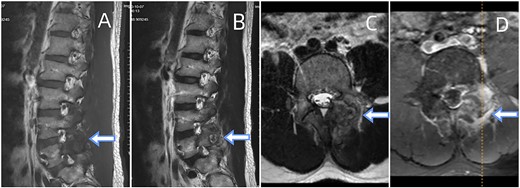

CT showed erosions in the facet joints over left L5-S1, with soft tissue masses and sclerotic margins (Fig. 1). MRI depicted a 1.8◊1.1 cm extra-dural mass in the left L5-S1 facet joints, displaying low signal on T1-weighted and high signal on T2-weighted imaging. Gadolinium contrast highlighted heterogeneous enhancement of the lesion (Fig. 2).

Depicts an MRI of the lumbar spine. (A) Sagittal sections of the T1-weighted. (B) A section of T2-weighted. (C) Axial section of the T2-weighted. (D) Contrast-enhanced T1-weighted. The presented images reveal an ovoid extra-dural mass measuring1.8◊1.1 cm at the subarticular area of the left L5-S1. This mass exhibits low signal intensity on T1-weighted (A) and hyperintense signal intensity on T2-weighted (B). Axial T2-weighted fat-suppressed with contrast enhancement is depicted at the L5-S1 level (C, D). The sequence illustrates a lesion that heterogeneously enhances and extends posteriorly from the left facet joint. Surrounding the L5-S1 left articular joint resection is a nodular chalky soft tissue mass.